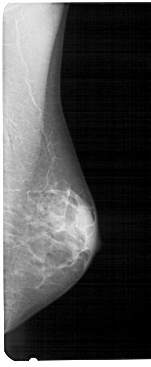

A_1937_1.RIGHT_MLO

RIGHT_MLO LINES 5491 PIXELS_PER_LINE 2251 BITS_PER_PIXEL 12 RESOLUTION 43.5 NON_OVERLAY